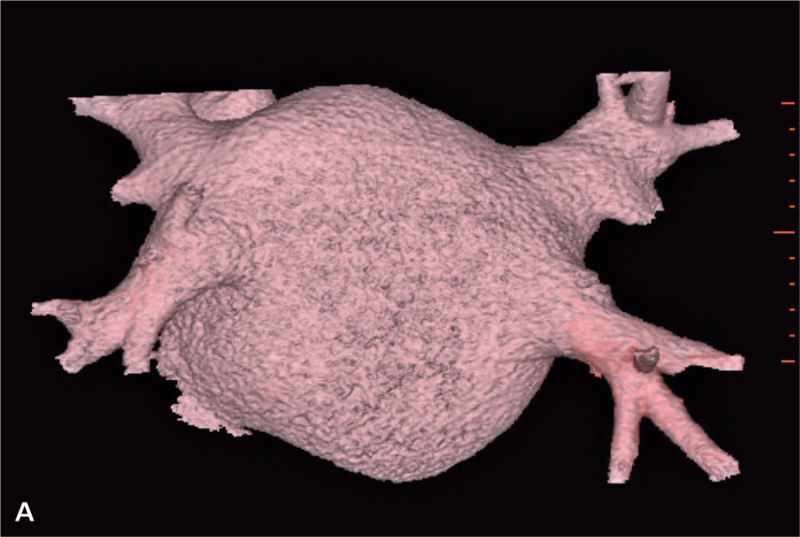

Po operacji wykonano kontrolne badanie TK serca, w którym nie stwierdzono zmian ogniskowych i zagęszczeń zapalnych w uwidocznionym miąższu płucnym. Przełyk oraz pozostałe uwidocznione badaniem struktury śródpiersia również były bez zmian. Uwidocznione węzły chłonne nie były powiększone. Badanie wykazało stan po plastyce przedsionka lewego oraz wszczepieniu sztucznego pierścienia w pierścień zastawki mitralnej. Objętość przedsionka po zabiegu wynosiła 129 cm3 (przed zabiegiem 186 cm3) (ryc. 1A, B, 2A, B).

RYCINA 2. Rekonstrukcja objętościowa (VR transparent) lewego przedsionka. [A] Przed operacją. [B] Po operacji.